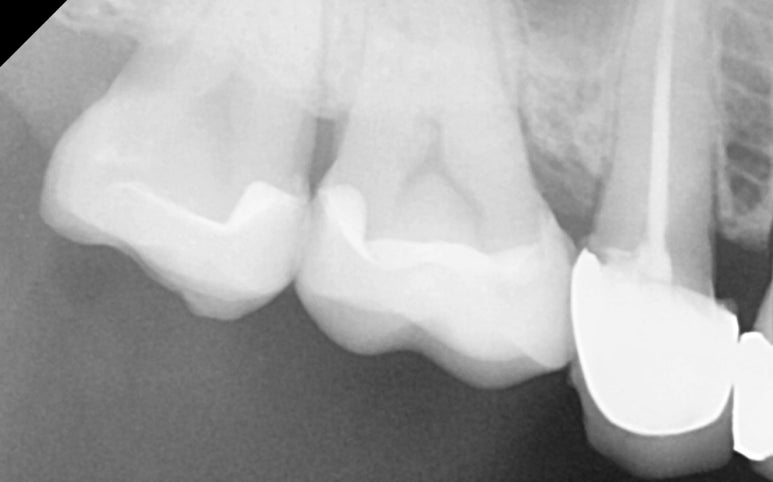

25.11.11 레진 코팅 후 엑스레이 사진

약 일주일 뒤,

기공소에서 정교하게 제작된

세라믹 수복물이 도착했습니다.